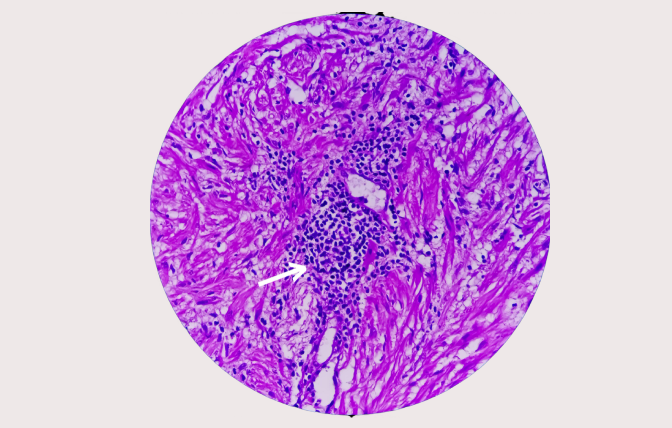

Prostate cancer

is a

malignant condition

characterized by the

abnormal growth of cells

in the

prostate gland

Prostate cancer is a common malignancy that forms in the prostate gland, located below the bladder in men. It develops when abnormal cells in the prostate grow uncontrollably, often without symptoms in the early stages.